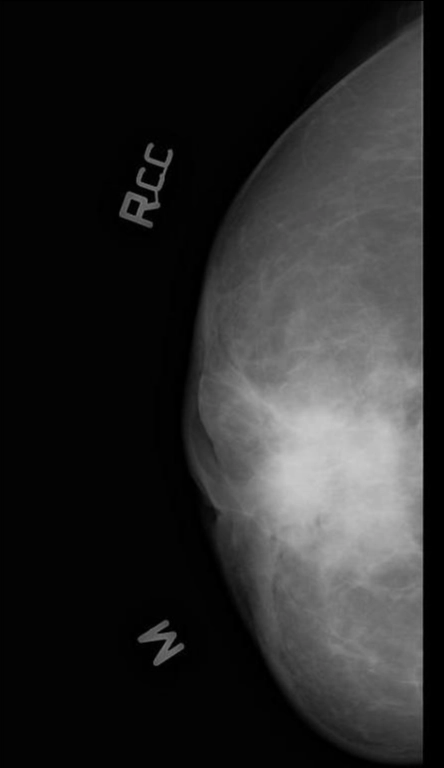

U ác tính

Ung thư biểu mô tuyến vú xâm nhập loại không đặc biệt (Invasive breast carcinoma of no special type)